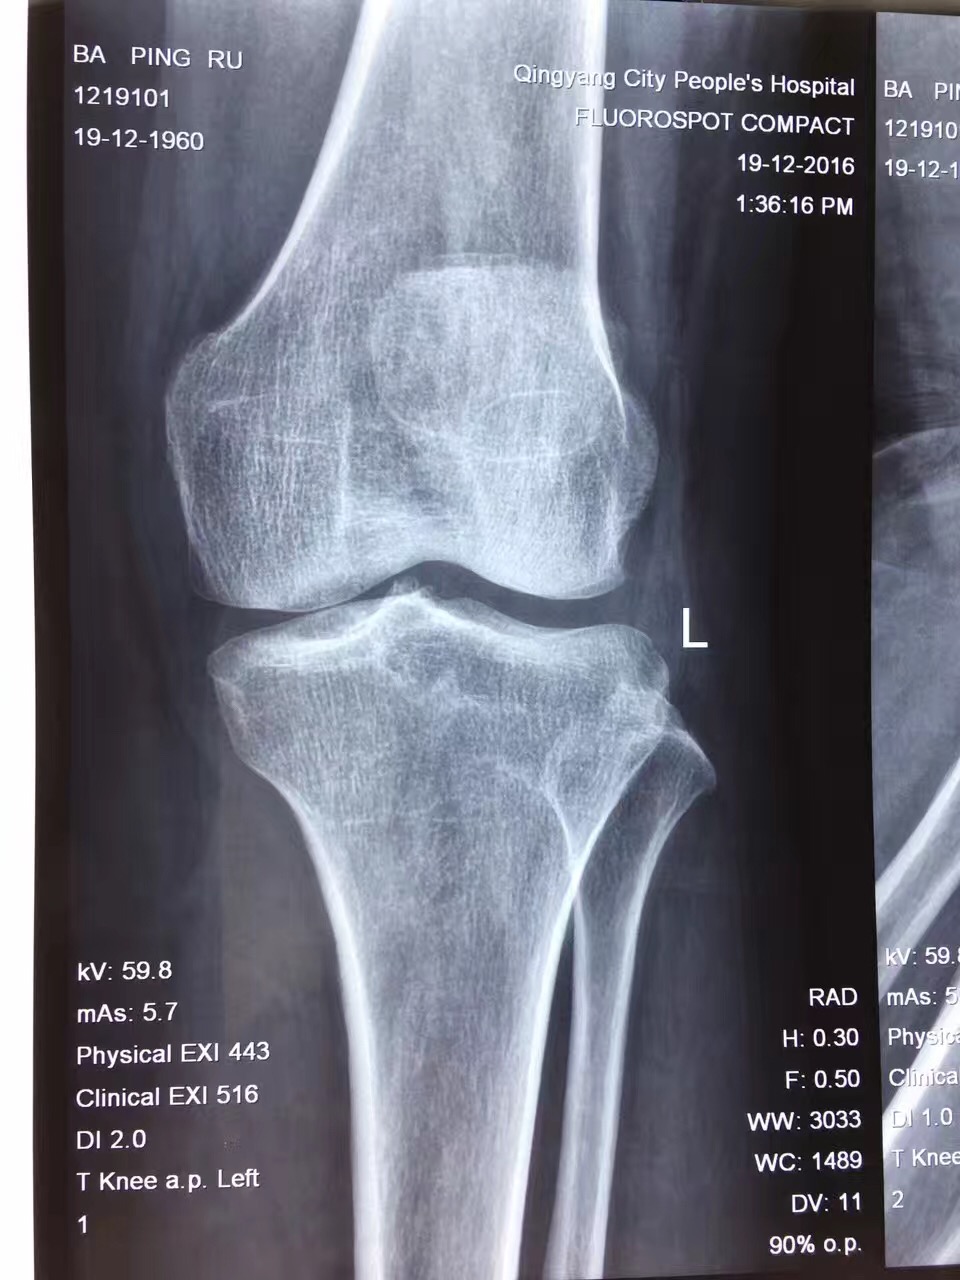

我院成功开展甘肃省首例牛津单髁膝关节置换术

我院骨三科于2017年成功自主开展我省首例牛津单髁关节置换术,目前已成功进行3例。单髁置换术具有损伤小、出血少、康复快、膝关节功能恢复良好、术后第二天即可下床、患者住院时间短、住院费用低等优势,为骨关节炎患者带来了福音。

近年来,骨性关节炎患者不断增多,其治疗往往采取“保守治疗等待全膝置换”或“直接全膝置换”。但并非所有的骨性关节炎患者都需要进行全膝置换才能解决问题。解剖学将膝关节分为三个间室:内侧间室、外侧间室、髌股关节间室,全膝置换能够解决所有三个间室的病变。临床数据显示,大约30%的患者膝关节病变只局限在一个间室,并未累及其他两个间室。这种情况下,我们是否可以只需要置换病变间室就可以解决问题?对于这些病人进行全膝置换是不是过度医疗?基于对不同时期的膝关节终末期患者制定个体化方案的理念,单髁置换术由此应运而生。